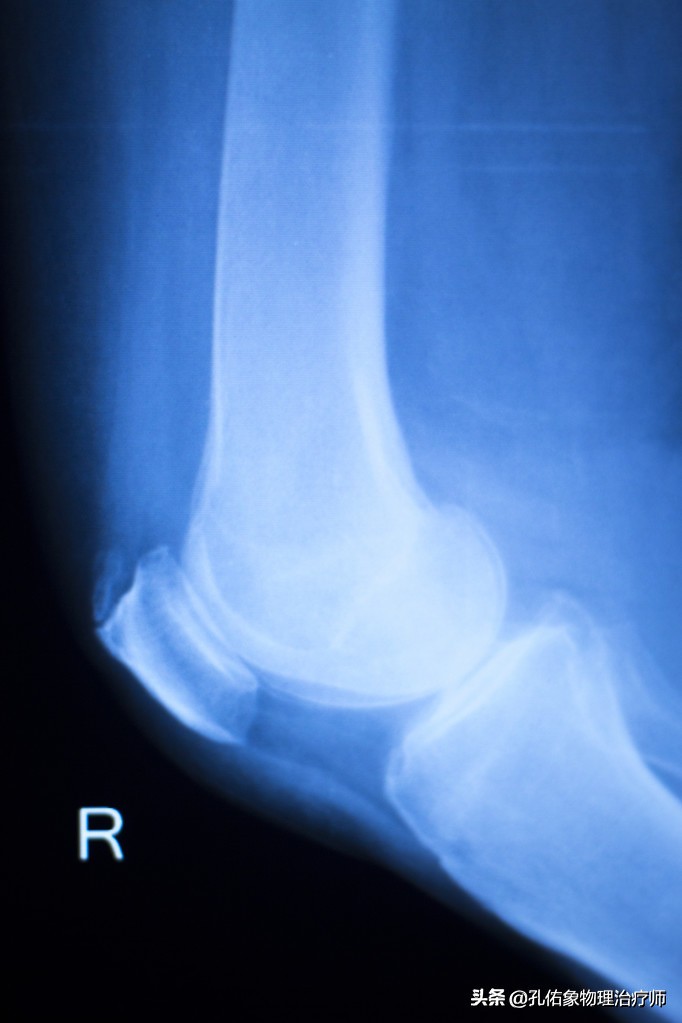

• 拍X片(轴位片)

膝关节痛骨性关节炎的治疗方法,膝骨性关节炎的手法治疗视频

一般在医院里边,很多医生也不会让患者去拍轴位片,都喜欢去拍正侧位片。但是对于膝痛早期的人而言,在下蹲过程中出现疼痛时的角度去拍轴位片,会发觉挺有意思的,膝盖骨是外移的,并没有在正常的髁间窝里边,这就是典型的膝盖骨软骨软化的表现。

这样的膝痛,在早期通过片子是很难发现的,所以你无论是做啥治疗,效果都不好。只有找到病因后,从根本的力学入手治疗才是上策。若是不及时治疗,使膝盖骨一直处于不正确的轨迹里面运动,最终膝痛厉害,活动受限,拍X正侧位片会显示膝盖骨边缘骨质增生、骨硬化改变及粗糙不平,膝盖骨关节间隙狭窄。